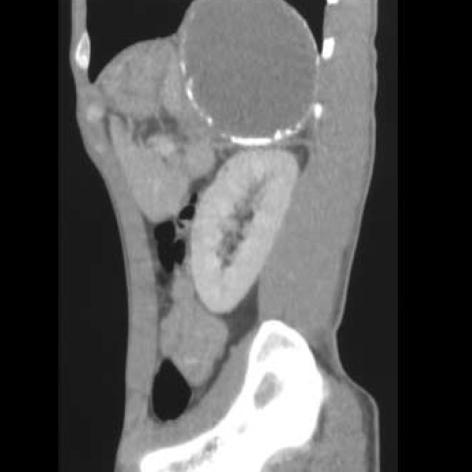

Infradiaphragmatic extralobar pulmonary sequestration is an extremely rare congenital malformation. It is more frequently diagnosed in the antenatal period due to routine ultrasonic examination of the fetus or in the first 6 months of life, though on rare occasions it is discovered incidentally in adults. A 32-yr-old man presenting with epigastric discomfort and fever was referred. Computed tomographic scanning showed that a 16-cm, multiseptated, dumbbell-shaped, huge cystic tumor was located beneath the diaphragm. On the next day, 850 mL of thick yellowish pus was drained by sonography-guided fine needle aspiration for the purpose of infection control and diagnosis, but no microscopic organisms were found in repeated culture studies. Surgical removal of the cyst was performed through thoracoabdominal incision and most of these pathologic lesions were removed but we could not find the feeding arteries or any fistulous tract to surrounding structures. Histopathologic study revealed that it was extralobar pulmonary sequestration and culture study showed that many WBC and necrotic materials were found but there were no microorganisms in the cystic contents. We report the first case of an infected infradiaphragmatic retroperitoneal extralobar sequestration which was administered a staged management and achieved an excellent clinical course.

膈下叶外型肺隔离症是一种极为罕见的先天性畸形。由于对胎儿进行常规超声检查,它在产前更常被诊断出来,或者在出生后的头6个月内被诊断,不过在极少数情况下,它是在成人中偶然发现的。一名32岁出现上腹部不适和发热的男子前来就诊。计算机断层扫描显示,一个16厘米、多分隔、哑铃状的巨大囊性肿瘤位于膈肌下方。第二天,通过超声引导下细针穿刺抽出850毫升浓稠的黄色脓液,以控制感染和进行诊断,但在反复培养研究中未发现微生物。通过胸腹联合切口对囊肿进行手术切除,大部分这些病理病变被切除,但我们未能找到供血动脉或与周围结构的任何瘘管。组织病理学研究显示这是叶外型肺隔离症,培养研究表明在囊内容物中发现了许多白细胞和坏死物质,但没有微生物。我们报告了首例接受分期治疗并取得良好临床过程的感染性膈下腹膜后叶外型肺隔离症病例。